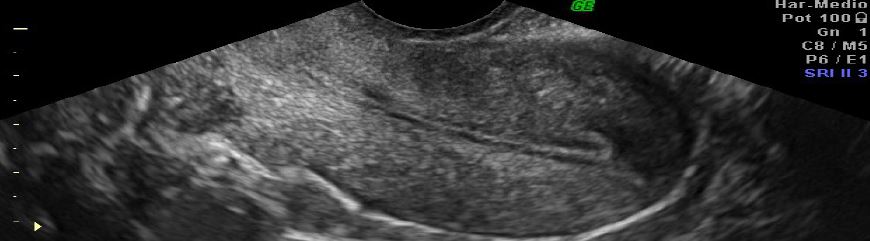

Luis Alonso Pacheco. Centro Gutenberg. Málaga. Spain INTRODUCTION Adenomyosis is defined as the presence of ectopic endometrial tissue inside theContinue Reading